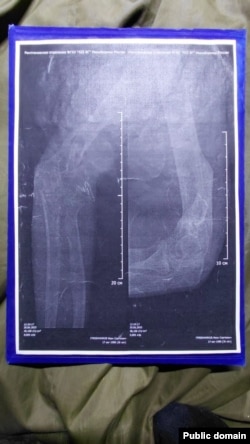

Снимки сломанной руки Ивана Гребенникова

– Нам казалось, что после возвращения из плена нас хотя бы лечить будут. Куда там – нам внаглую поменяли категории на фальшивые – мне, например, мою "Д" заменили на "Б" (годен к службе с незначительными ограничениями), хотя у меня правая рука как была в нескольких местах перебита, так и висит. У меня до сих пор пуля в теле – даже не оперировали, – говорит Иван. – И нас таких очень много – на костылях, в гипсе. Им просто по**й, везут на Донецкое направление калек.